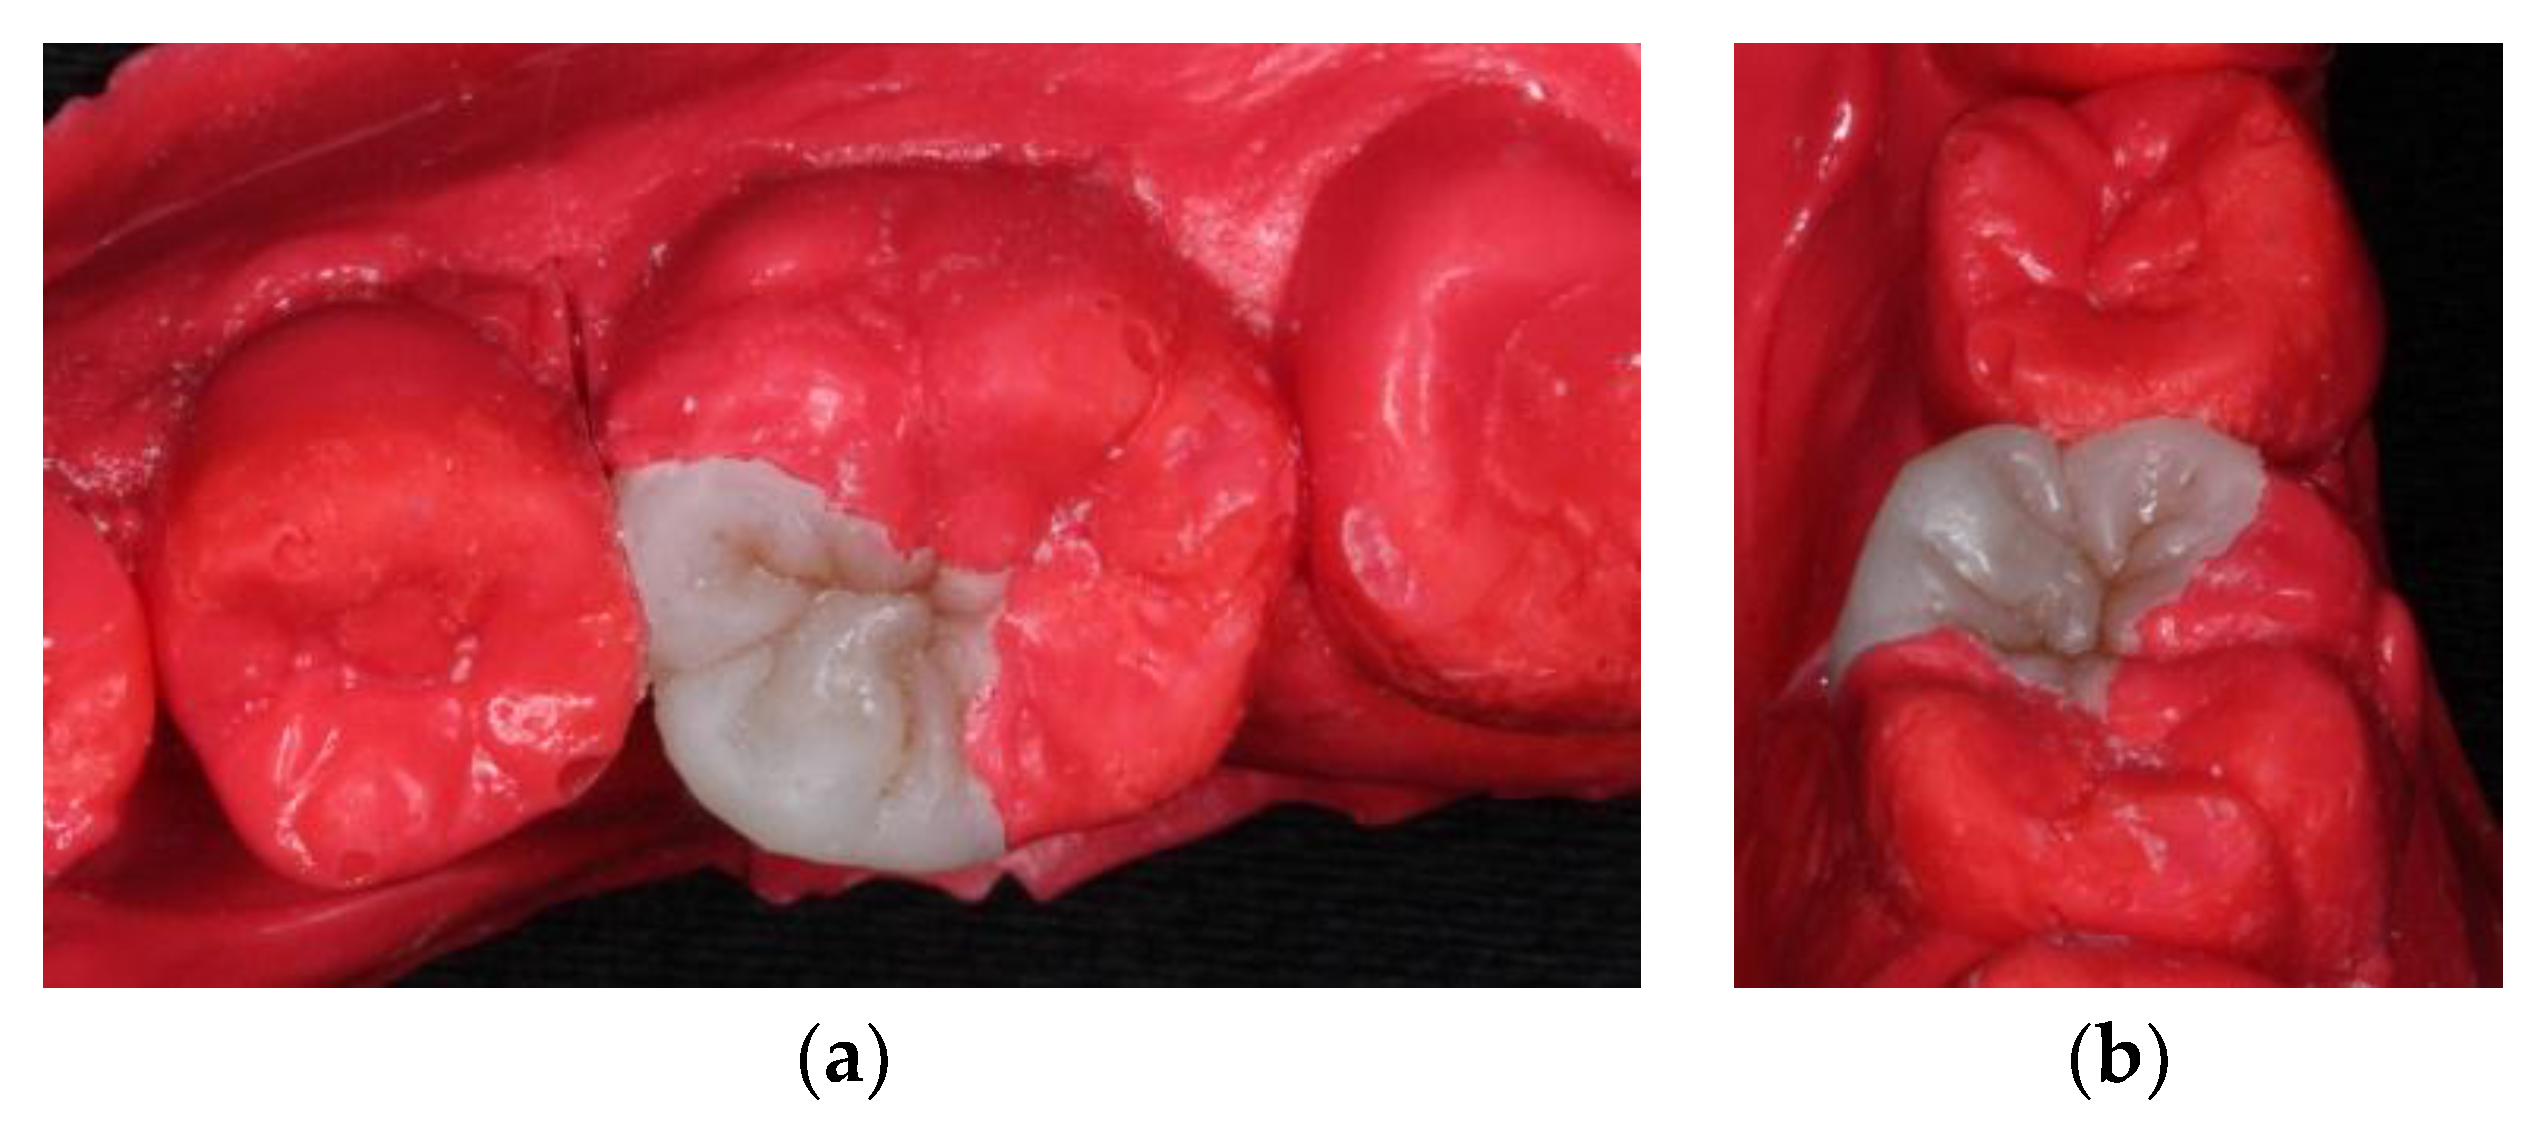

Figure 3). The mesial gingival margin was located approximately 0.5 mm subgingivally. Therefore, gingival displacement was achieved using a retraction cord. The undercuts of the tooth cavity were blocked out with a nano-hybrid composite resin (Grandio, shade A3, Voco, Cuxhaven, Germany), which served as a base material. The cavity was prepared, and an alginate impression was taken after removal of the rubber dam. A self-cured bis-acrylic resin (Structur 2 SC, Voco, Cuxhaven, Germany) was used as a temporary filling material before the next cementation appointment. A fast-setting silicone die material (GrandioSO Inlay System, Voco, Cuxhaven, Germany) was injected into the alginate. During the inter-appointment period, the onlay restoration was fabricated incrementally with a light-cured composite resin (Grandio, shades A2, A3, and A3.5, Cuxhaven, Germany) (

Figure 4), and each layer was polymerized for 10 s with a light-emitting diode curing unit (Valo, Ultradent, South Jordan, UT, USA) with light irradiance of 1000 mW/cm

2. For sculpting the occlusal morphology, we determined mesio-lingual cusp and trianglular ridge by referring to the existing distolingual cusp and neighboring teeth. In addition, the cast of the upper arch was used for adjusting the occlusion. The final occlusal anatomy was reconstructed and incorporated with a resin staining kit (Tetric color, Ivoclar Vivadent, Schaan, Liechtenstein), which was used for internal staining to mimic the fissures of a natural tooth. After finishing and polymerization, the composite onlay was removed from the silicone die and cured from the intaglio surface for 40 s.